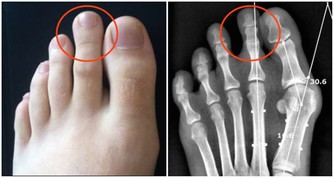

你們有沒有發現,長痘痘就喜歡就那幾個經常長的位置反复長,就好像那個地方埋下了種子一樣,一顆好了,一顆又長,簡直煩死了

這其實是因為經常長痘的那塊區域,有害菌多過有益菌!